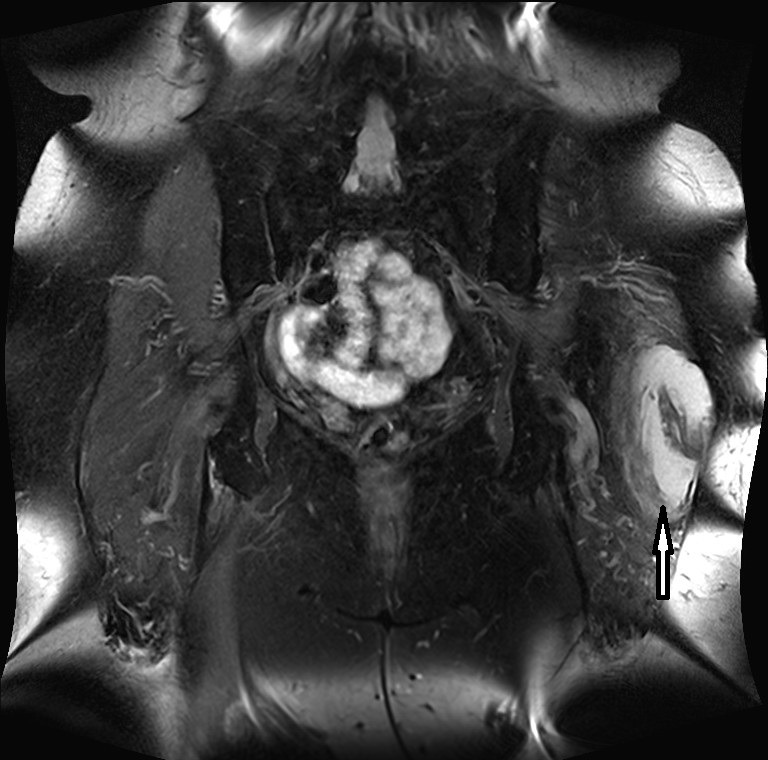

This is the first report on a localized pigmented villo-nodular synovitis (PVNS or TSGCT) occurring in the trochanteric bursa. Bursal involvement in PVNS is extremely rare. Most often PVNS occurs either as a localized or diffuse lesion in a major synovial joint, such as the knee, ankle joint or hip joint. In principle, all synovial structures can be involved. The case reported here is remarkable regarding the long period between the occurrence of the first symptoms and the final diagnosis as well as the age of the female patient (75 yrs). Therapeutically a complete resection was performed in order to avoid recurrence. More then three years later the patient did well and there has been no evidence of recurrence yet.